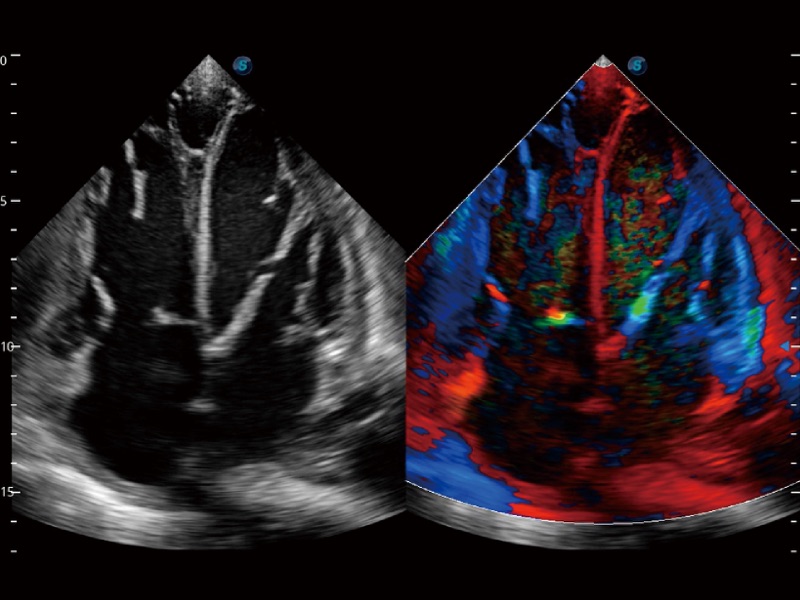

心血管应用

支持运动和药物负荷协议、多心动周期存储选择,为临床观察心肌负荷状态下的室壁节段运动、评估心肌缺血状态提供更多的解决方案。

通过心肌识别技术和二维斑点追踪技术相结合,计算心肌各节段的应变应变率、速度、位移并以曲线图显示,实现整体或者局部心肌定量分析。同时可呈现牛眼图直观和准确诊断心肌的运动情况。